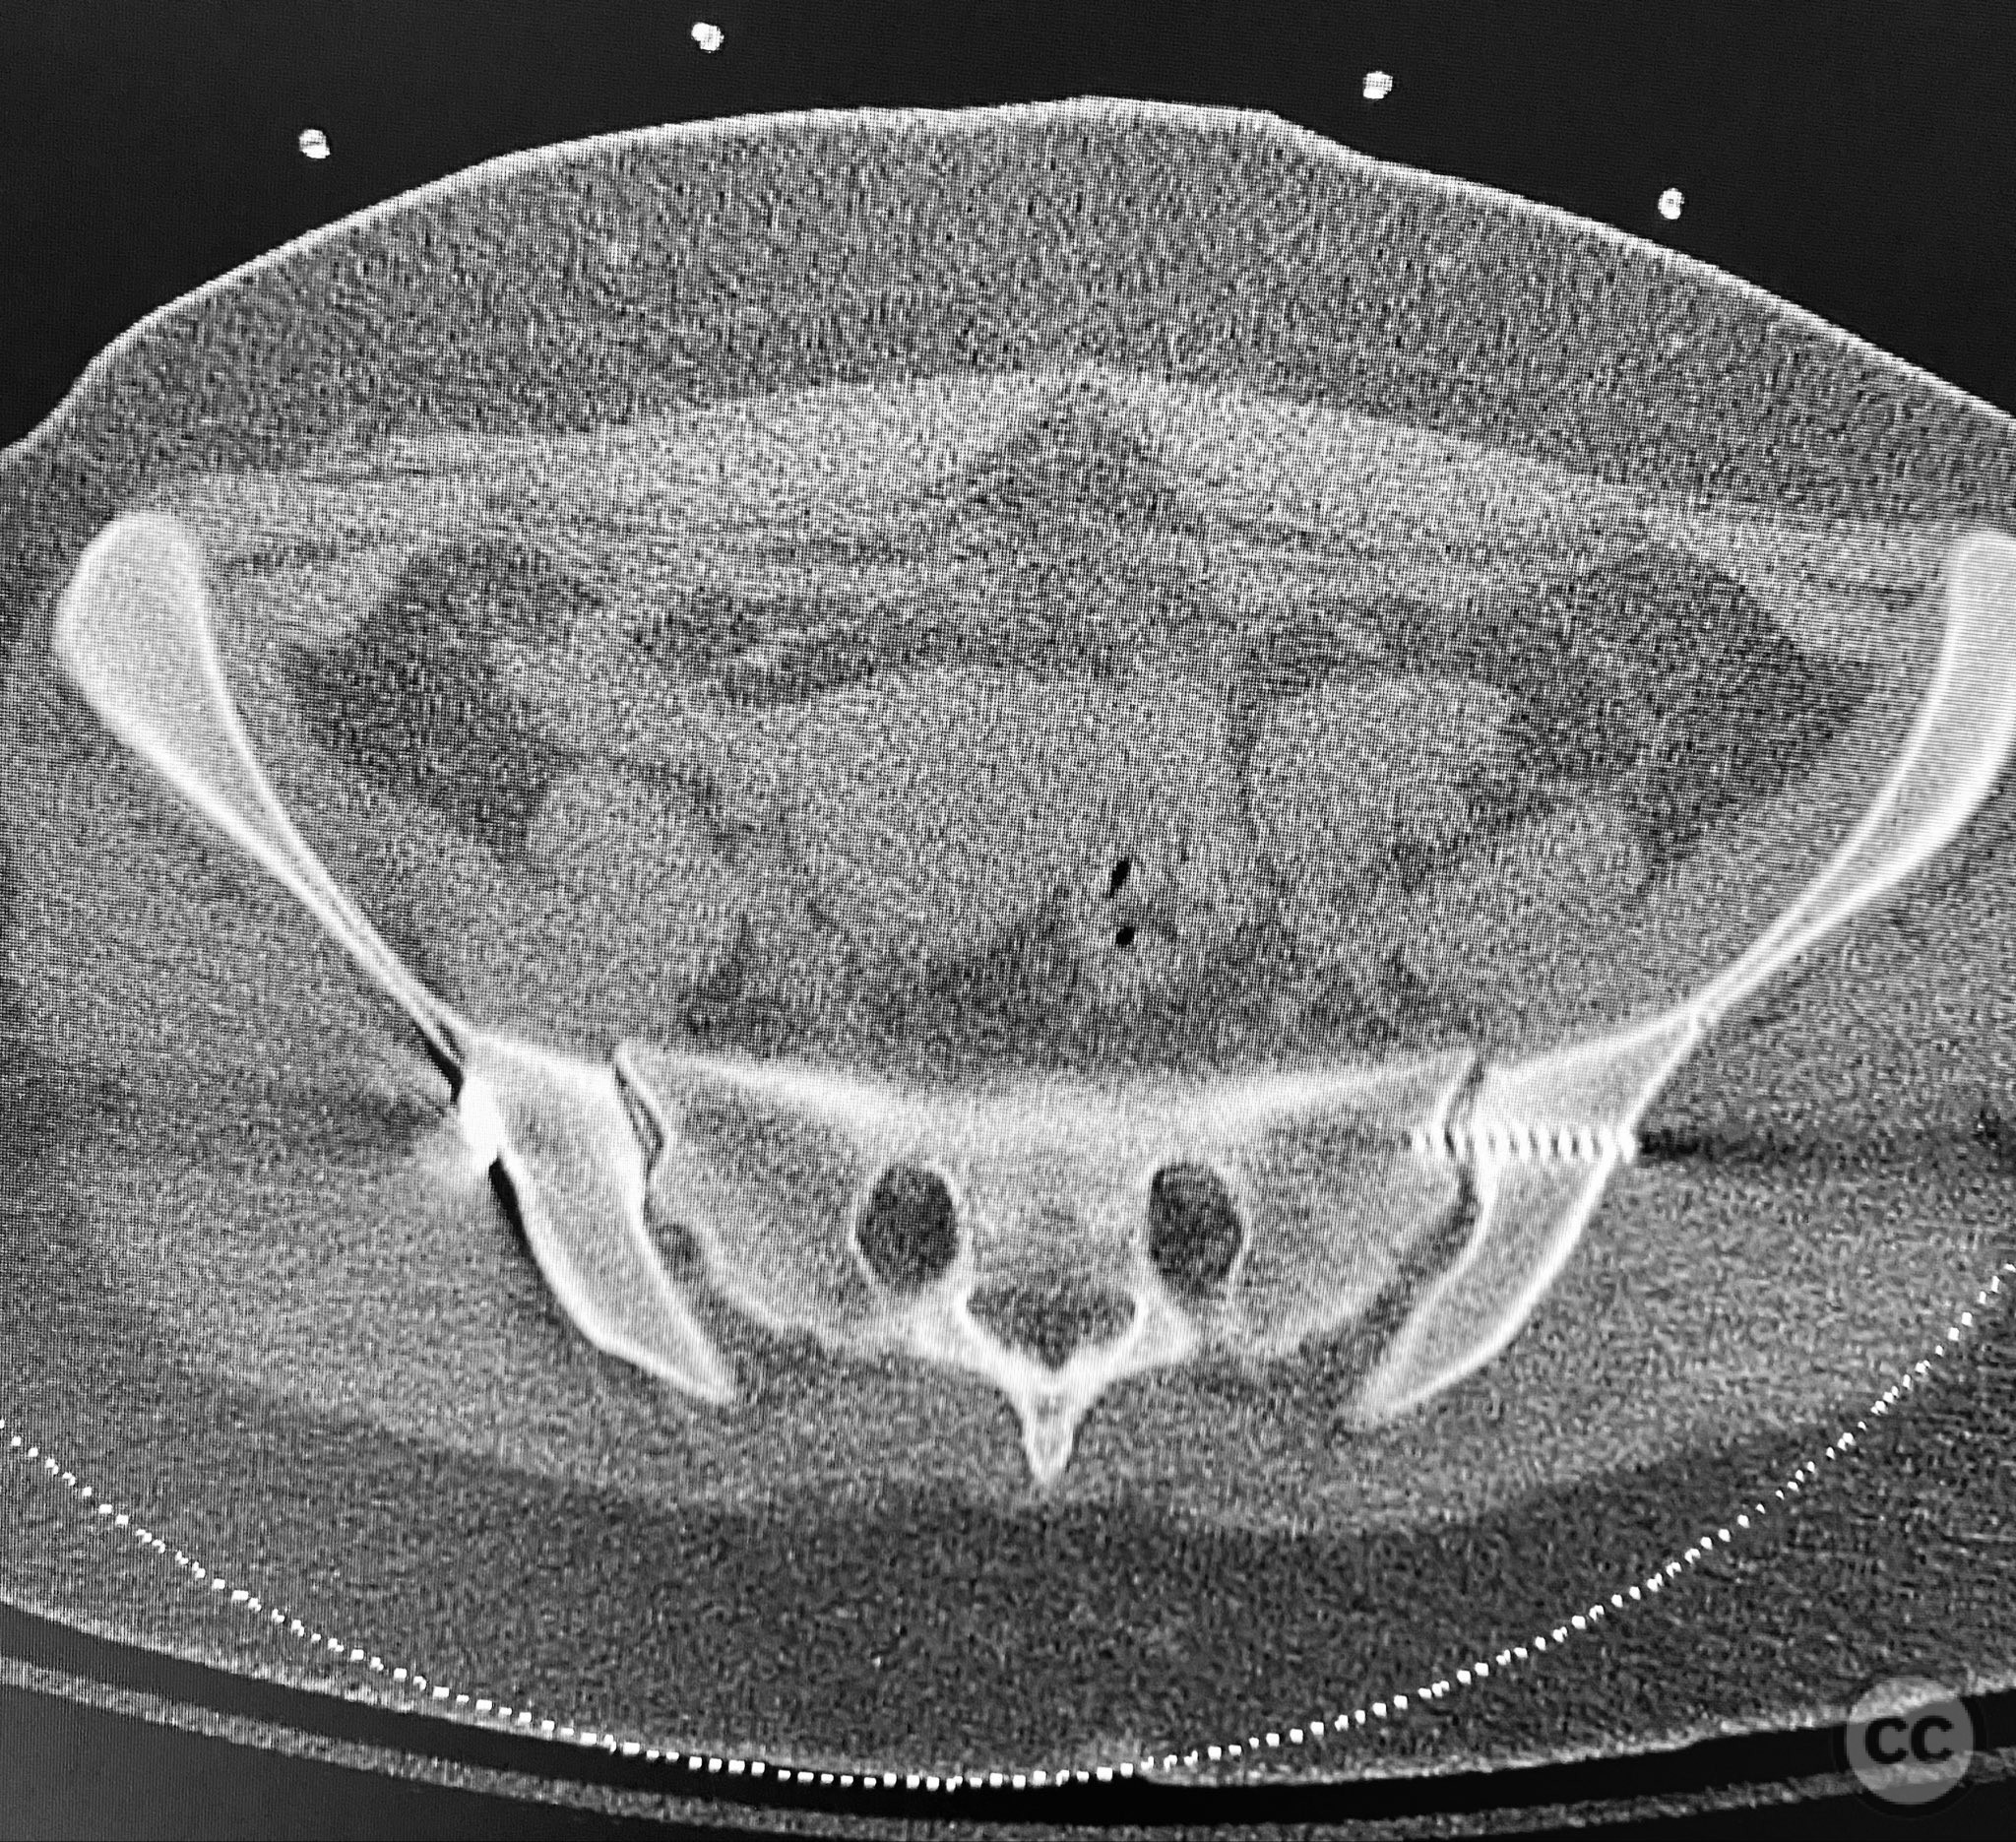

Clinical and radiological findings:  A young adult female sustained a high-energy pelvic injury following a motorcycle crash. She was hemodynamically stable on presentation, with normal neurovascular examination and no evidence of genitourinary, vaginal, or rectal injury. She reported pain localized to both anterior and posterior pelvic regions. Initial plain radiographs (with and without pelvic binder) demonstrated multiple anterior ring fractures and dislocations. The binder images obscured the full extent of injury. Further intraoperative fluoroscopic imaging (AP, inlet, and with lower extremities in "lotus" position) revealed bilateral sacroiliac (SI) joint disruptions (right greater than left), bilateral superior/inferior pubic ramus fractures (right greater than left), and symphyseal diastasis. Notably, the right pubic ramus demonstrated excessive curvature, complicating potential percutaneous screw fixation. AO/OTA classification: 61-C1.3 (bilateral complete disruption of the posterior arch with associated anterior ring injury). Young-Burgess classification: APC III.

Planning remarks:  The preoperative plan included open reduction and internal fixation (ORIF) of the displaced right pubic ramus fracture and symphyseal diastasis via an anterior approach, with acceptance of indirect closed reduction of the SI joints. Percutaneous trans-sacral screw fixation was planned for stabilization of the posterior pelvic ring. Due to the complex curvature of the right ramus, straight screw fixation was deemed unsuitable.

Anatomical surgical approach:  A combined Pfannenstiel and intrapelvic (modified Stoppa) approach was utilized. A transverse suprapubic skin incision was made approximately two fingerbreadths above the symphysis pubis. Dissection proceeded through the subcutaneous tissue and rectus sheath, with careful subperiosteal elevation of the rectus abdominis from the anterior pelvic ring. The retropubic space (Cave of Retzius) was developed to expose the symphysis pubis and superior pubic rami bilaterally. Intrapelvic exposure allowed direct visualization and reduction of the displaced right pubic ramus fracture and symphyseal diastasis. A pre-contoured plate was applied to the anterior ring using both direct and indirect reduction techniques.

Intraoperative fluoroscopy with AP and inlet views, as well as dynamic positioning of the lower extremities, was critical in fully delineating the extent of injury, which had been underestimated on preoperative imaging due to binder application. The excessively curved morphology of the right pubic ramus precluded safe or effective straight screw fixation; therefore, ORIF with a contoured plate was performed using intrapelvic exposure for optimal fit and stability. Indirect closed reduction of the SI joints was accepted, followed by percutaneous trans-sacral screw fixation under fluoroscopic guidance. This case highlights the necessity of thorough intraoperative assessment for occult or underestimated injury patterns in complex pelvic trauma, particularly when initial imaging is performed with a pelvic binder in situ.